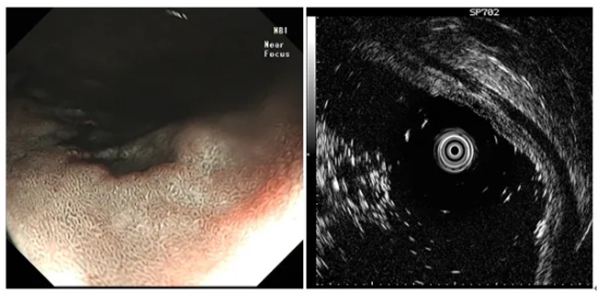

圖示超聲內(nei)鏡掃查直腸腫物(wù)及(ji)縱膈

微信(xin)截圖_20240417142405.jpg